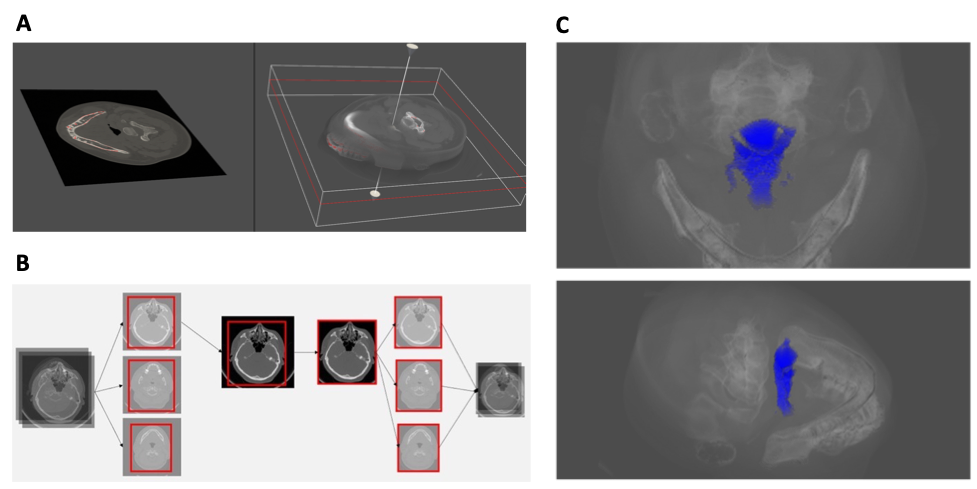

Rationale| The incidence of clinically undiagnosed obstructive sleep apnea (OSA) is high among the general population due to limited access to polysomnography. Computed tomography (CT) of craniofacial regions obtained for other purposes can be beneficial in predicting OSA and its severity. Objectives| To predict OSA and its severity based on paranasal CT using a 3-dimensional deep learning algorithm. Methods| One internal dataset (n=798) and two external datasets (n=135 and 85) were used in this study. In the internal dataset, 92 normal, 159 mild, 201 moderate, and 346 severe OSA participants were enrolled to derive the deep learning model. A multimodal deep learning model was elicited from the connection between a 3-dimensional convolutional neural network (CNN)-based part treating unstructured data (CT images) and a multi-layer perceptron (MLP)-based part treating structured data (age, sex, and body mass index) to predict OSA and its severity. Measurements and Main Results| In four-class classification for predicting the severity of OSA, the AirwayNet-MM-H model (multimodal model with airway-highlighting preprocessing algorithm) showed an average accuracy of 87.6% (95% confidence interval [CI] 86.8–88.6) in the internal dataset and 84.0% (95% CI 83.0–85.1) and 86.3% (95% CI 85.3-87.3) in the two external datasets, respectively. In the two-class classification for predicting significant OSA (moderate to severe OSA), The area under the receiver operating characteristics (AUROC), accuracy, sensitivity, specificity, and F1 score were 0.910 (95% CI 0.899–0.922), 91.0% (95% CI 90.1–91.9), 89.9% (95% CI 88.8–90.9), 93.5% (95% CI 92.7–94.3), and 93.2% (95% CI 92.5–93.9), respectively, in the internal dataset. Furthermore, the diagnostic performance of the Airway Net-MM-H model outperformed that of the other six state-of-the-art deep learning models in terms of accuracy for both four- and two-class classifications and AUROC for two-class classification (p<0.001). Conclusions| A novel deep learning model, including a multimodal deep learning model and an airway-highlighting preprocessing algorithm from CT images obtained for other purposes, can provide significantly precise outcomes for OSA diagnosis